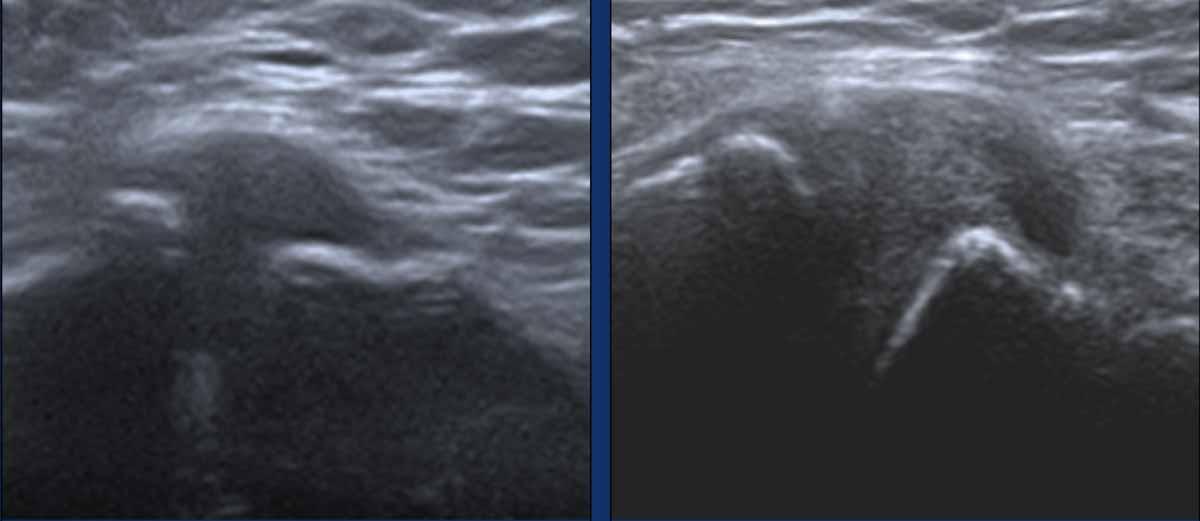

Hai ví dụ về gân đầu dài cơ nhị đầu bị dày lên.

Lưu ý hình ảnh echo không đều đặn, đặc biệt ở hình bên phải.

Có tăng sinh mạch máu và một ít dịch xung quanh (mũi tên).